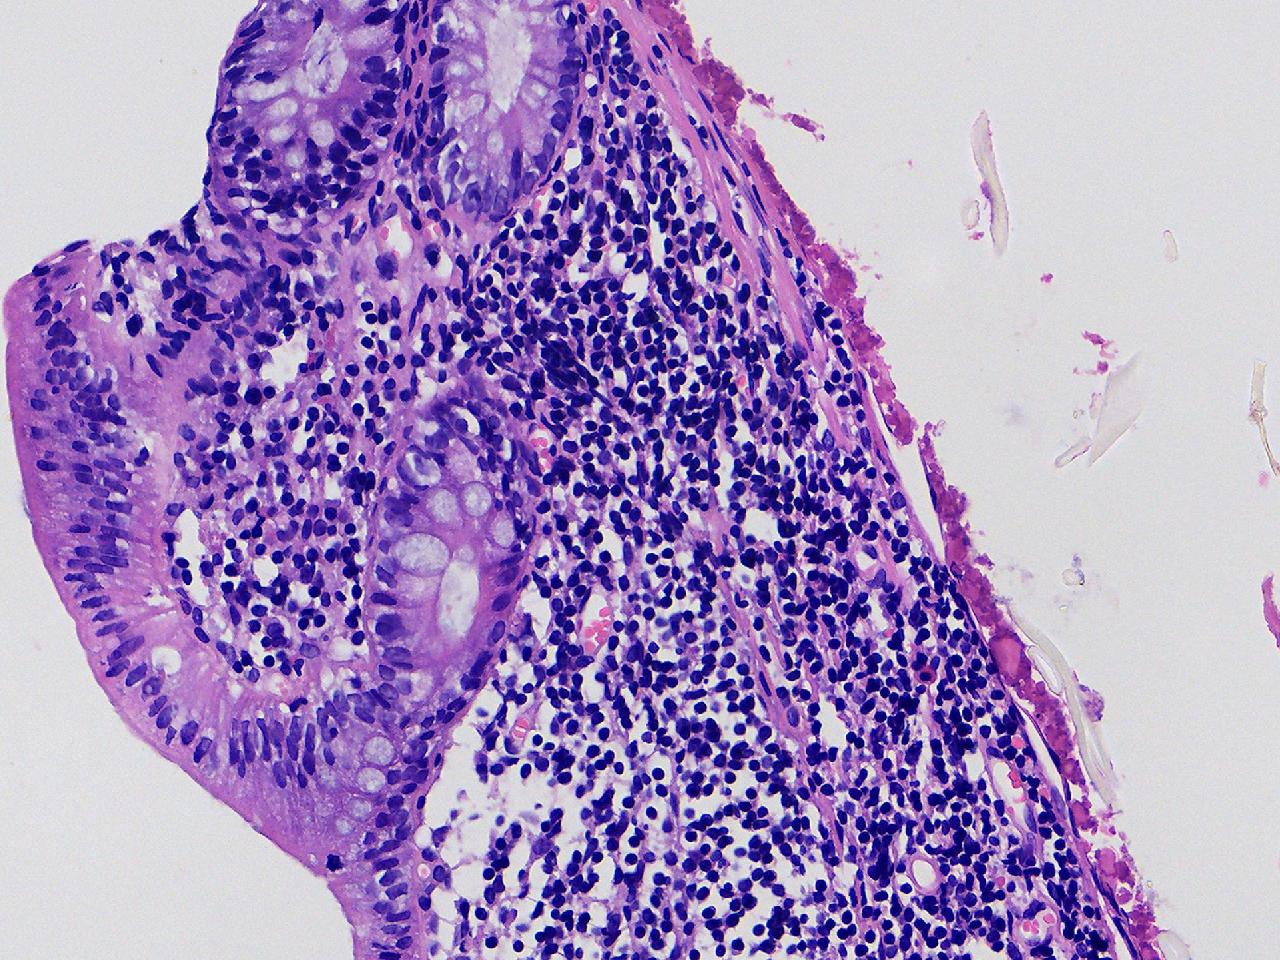

可见淋巴组织增生? 炎性?

性别

女

年龄

75岁

临床诊断

肠镜活检

一般病史

升结肠.降结肠.乙状结肠.直肠见多发直径约0.2—0.3厘米大小不等的扁平及指状隆起,表面光滑,升结肠取材1块。

标本名称

乙状结肠处活检

大体所见

灰白色不整形软组织1块。

粘膜慢性炎,局部淋巴组织增生。